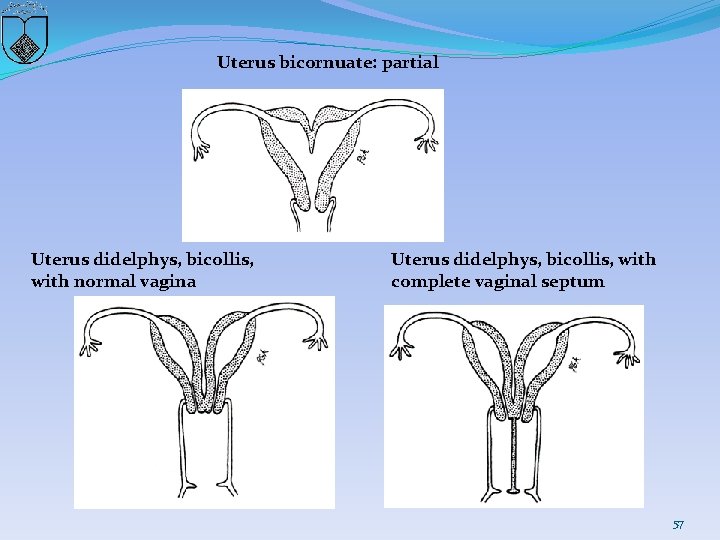

Uterus bicornuate: partial Uterus didelphys, bicollis, with normal vagina Uterus didelphys, bicollis, with complete vaginal septum 57